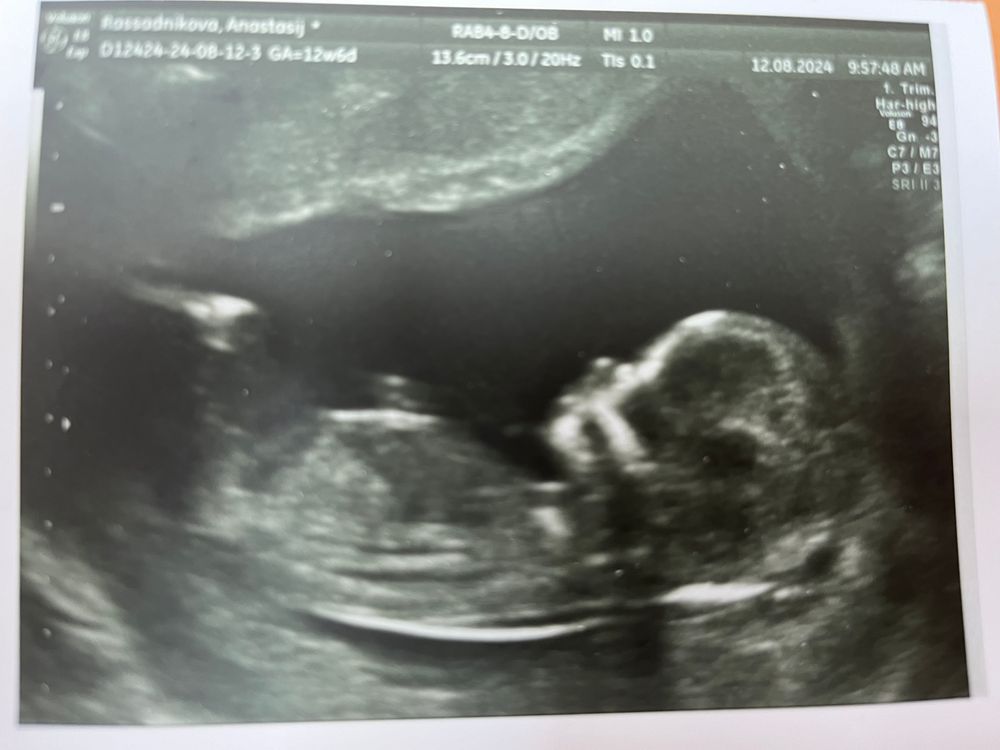

1-й скрининг)

Результаты УЗИВсем привет.Сегодня прошла первый скрининг. С пупсом все вроде хорошо по узи,жду кровь.🙏❤️

немного расстроили высокие значения маточных артерий🙁пока не буду расстраиваться, жду риски и кровь,тогда уже если надо буду переживать,а так пока рада что с крошкой все хорошо)))